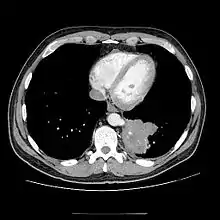

CT

Chest CT showing pulmonary sequestration

• CT scans have 90% accuracy in the diagnosis of pulmonary sequestration.

• The most common appearance is a solid mass that may be homogeneous or heterogeneous, sometimes with cystic changes.

• Less frequent findings include a large cavitary lesion with an air-fluid level, a collection of many small cystic lesions containing air or fluid, or a well-defined cystic mass.

• Emphysematous changes at the margin of the lesion are characteristic and may not be visible on the chest radiograph.

• CT technique for optimal depiction of lesions by using state-of-the-art volumetric scanning requires a fast intravenous (IV) contrast injection rate and appropriate volume and delay based upon size.

• Multiplanar and 3D reconstructions are helpful.